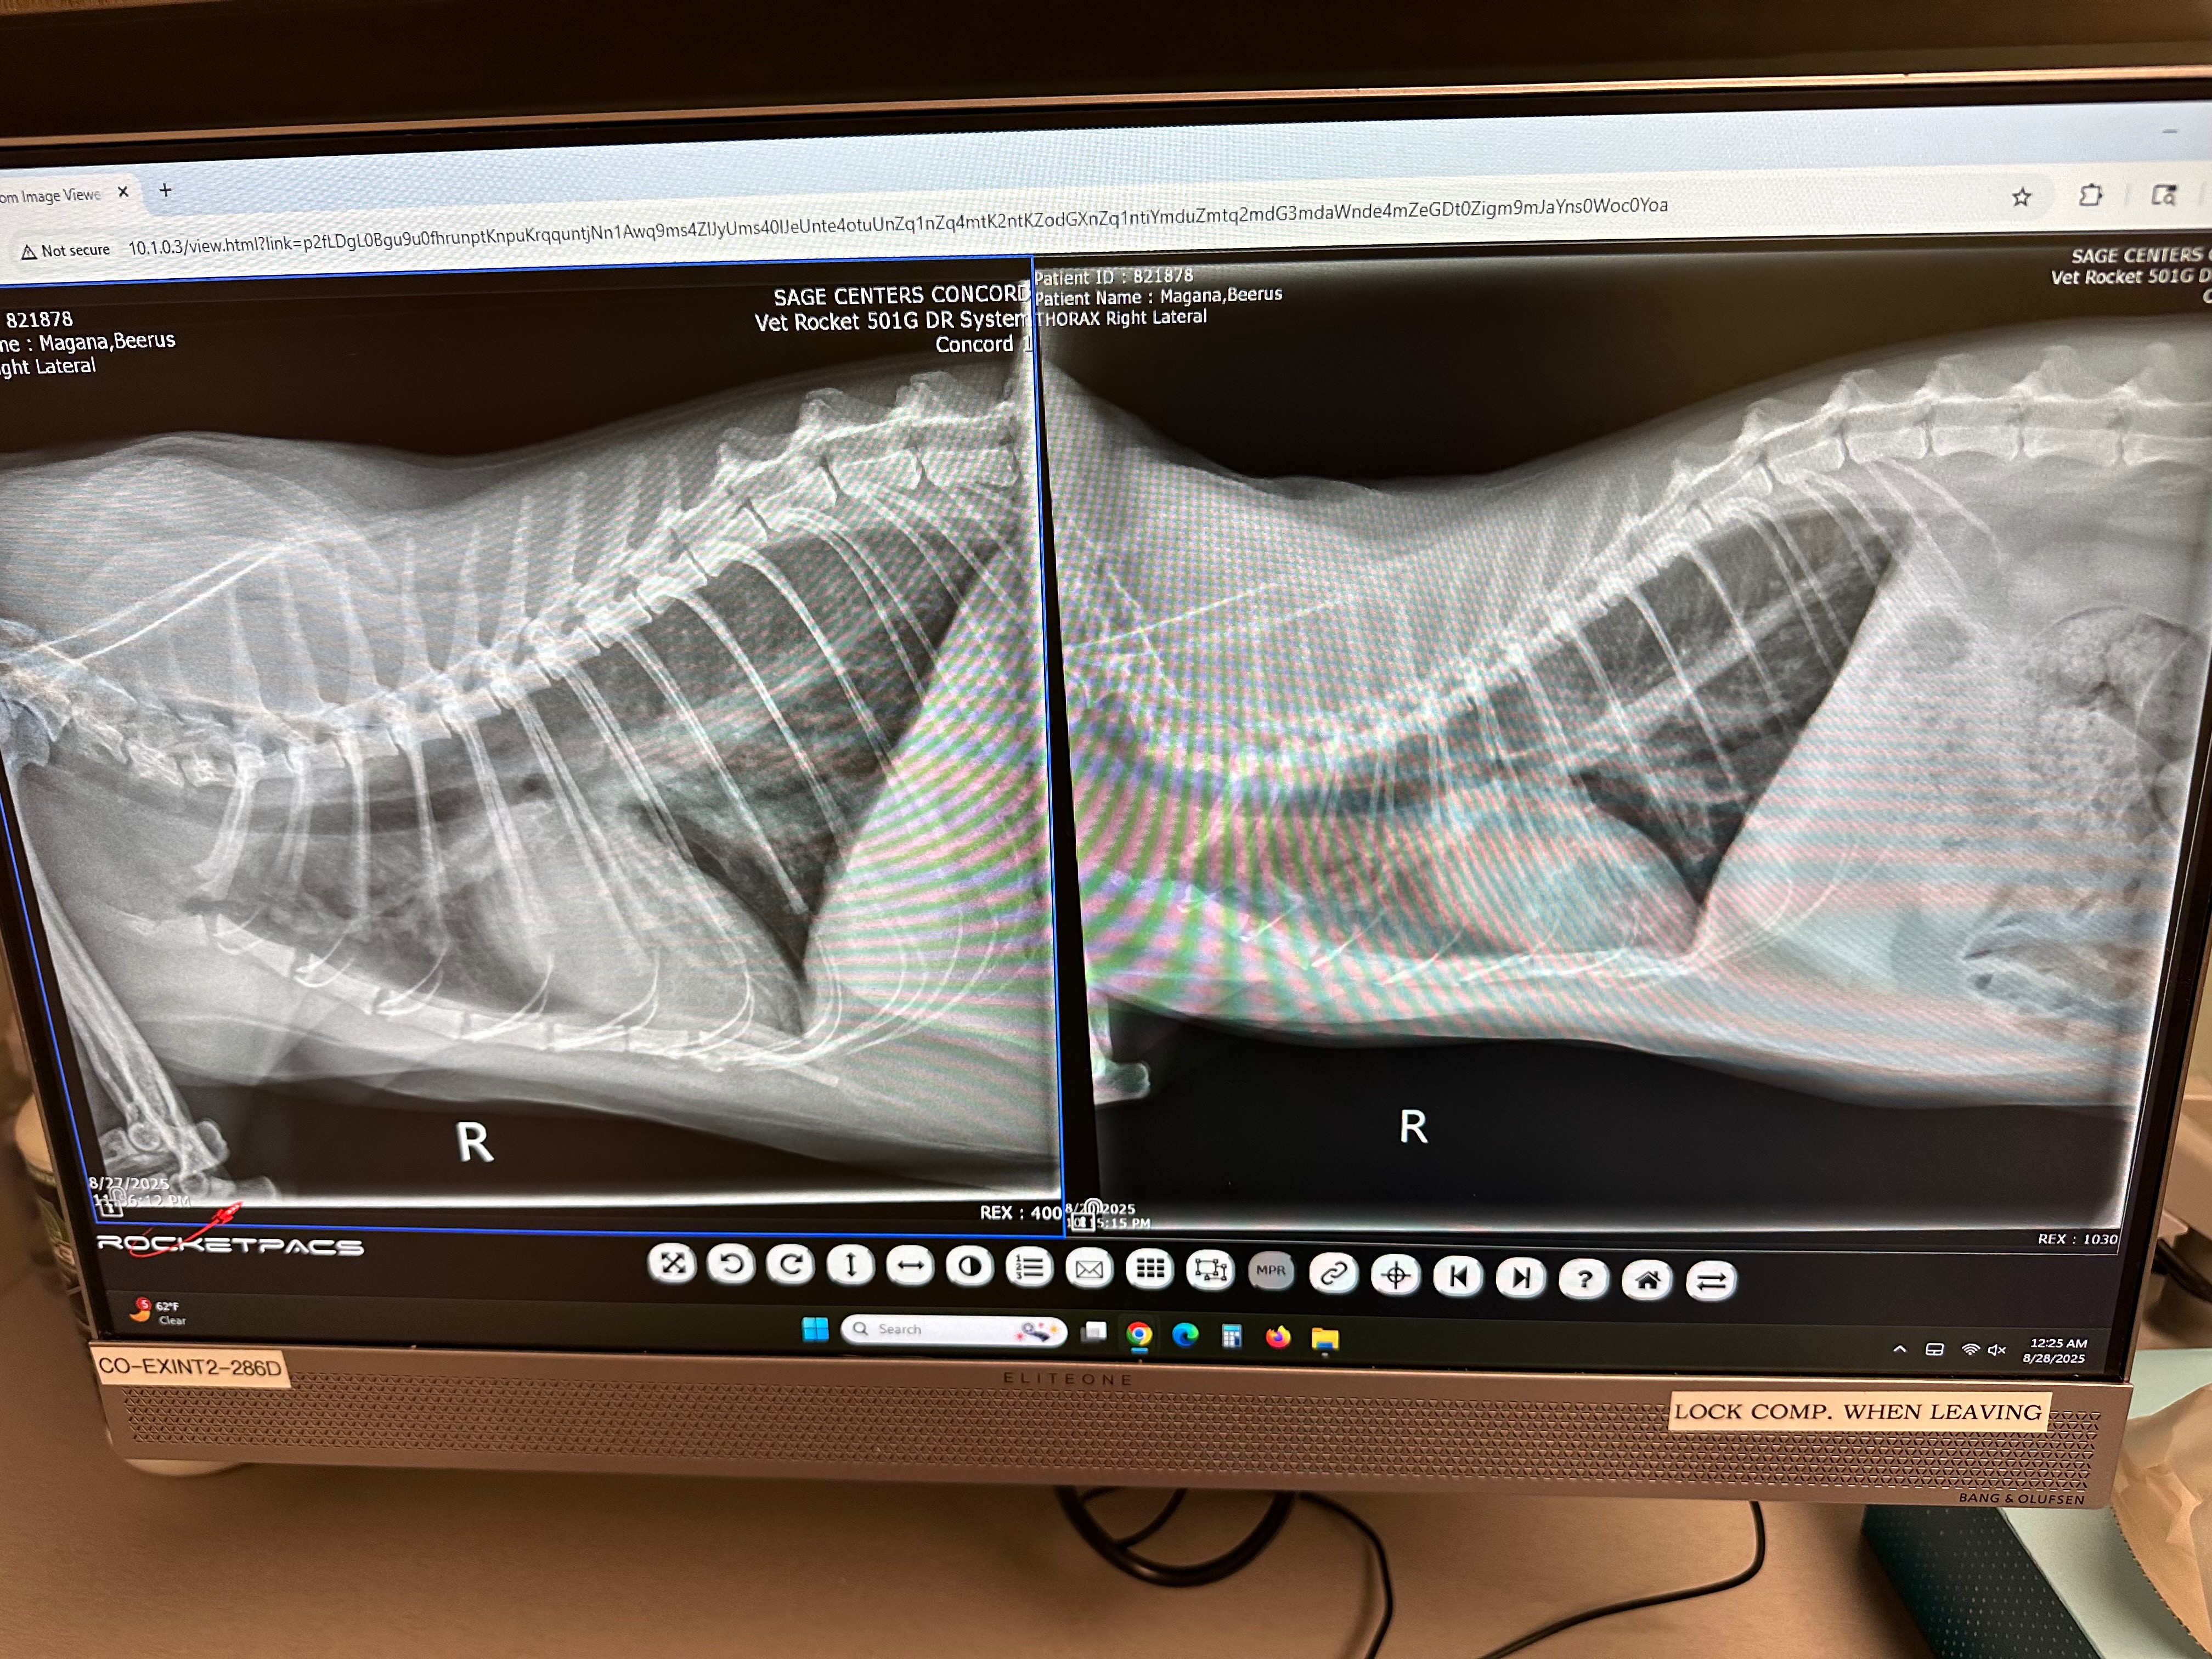

I am starting this fundraiser for my tiny son Beerus. He brings me so much joy and happiness. He helps me with my everyday battle of anxiety and depression. His sickness started from having a mild cough to finding out he has a heart murmur.

On 2024 I found out he has mild HCM and was scheduled to have an echocardiogram recheck in 6 months. During his recheck they saw fluid in his heart, diagnosing him with congestive heart failure. With all these new medications 3Xs a day and an echocardiogram recheck every 2 months, the vet and medications bills are taking a toll on me.

*Update* Beerus is still currently stable and the diuretics keeps increasing. I’m still in a financial burden and can’t keep up with all of these hospital bills.. I want to give him the life he deserves.. I greatly appreciate everyone who continues to contribute helping me save his life❤️‍